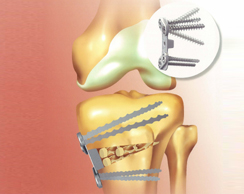

Opening Wedge Plate (Arthrex社):さらに近年、最新の最小のプレートのOpenig Wedge Plateが開発されました。小さいプレートにも関わらず、ねじの刺入方向の自由度が大きく、かつねじがワッシャーにより強固にロックする画期的プレートです。傷も小さく、かつ固定力も非常に上がっていますので、入院は1~2週間で退院できます。2週間目で膝は130度以上曲がり、2週目以後1/3の荷重を許可でき、骨癒合が良好であれば4週間で松葉杖を除去できます。最小は5cmの傷でできます。

Opening Wedge Plate